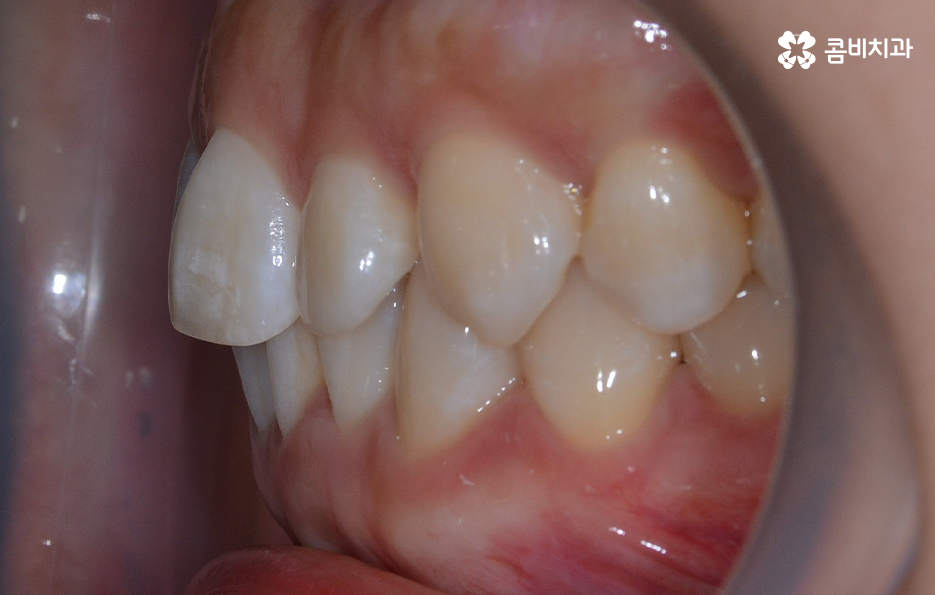

그렇기 때문에 비발치치아교정이 좋다고 생각하기 보다는 개인에 따라서는 치아의 이동 공간 확보를 충분히 하기 위해 발치가 필요한 경우도 있고 얼굴 변화나 부정교합의 개선을 위해 발치가 필수적인 경우도 있을 거예요

반면에 비발치치아교정으로도 충분히 좋은 결과를 얻을 수 있는 경우도 있을텐데 이러한 치료 과정 상의 특징과 장단점을 고려하여 자신의 치료 계획을 경험 많고 숙련된 교정 전문의와 잘 상의하실 필요가 있어요

아무래도 중년에 비해 성장기 혹은 20대 전후에 전신건강의 상태나 잇몸 상태가 더 좋은 경우가 많다면 중년 이후에는 잇몸이 약해질 확률이 더 높기 때문에 치료를 더 여유있는 기간을 두고 진행하고 숙련된 교정 전문의와 함께한다면 잇몸이 약해질 확률을 크게 줄일 수 있을 거예요.